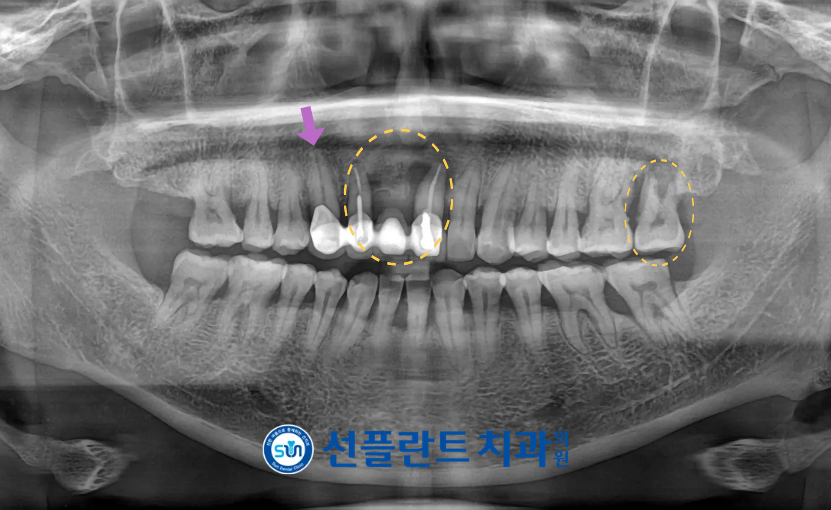

정밀한 검사를 위해

파노라마 사진을

촬영해 보았더니

위턱 앞니(#12,21)와

왼쪽 두 번째 큰 어금니(#27)가

뿌리 끝 염증으로 인해

주변 치조골 소실이 확인되었으며

안타깝지만 예후가 좋지 않아

발치가 불가피한 상황이었는데요.

위턱 앞니의 경우

보라색 화살표 표시의

오른쪽 송곳니(#13)와

보철물이 연결되어 있는 상태였지만

송곳니의 상태는 양호하였기 때문에

.

보철물 제거 후

예후가 좋지 않은 앞니(#12,11)은 발치하고

송곳니(#13)는 따로 크라운 수복을

진행하기로 하였습니다.